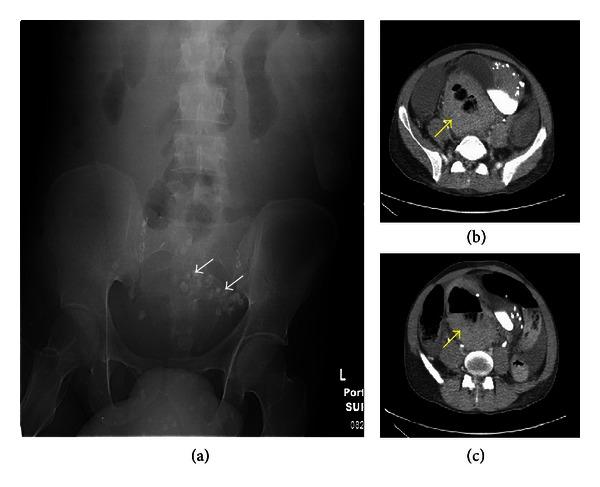

Klippel-Trenaunay syndrome (KTS) is a rare congenital syndrome of vascular malformations and soft tissue and bone hypertrophy. Vascular malformations can affect multiple organ systems. Involvement of the gastrointestinal (GI) tract is uncommon in KTS, but it can be a source of life-threatening bleeding. We report a case of a 32-year-old male with a known diagnosis of KTS who presented with a life-threatening rectal bleeding and was treated with proctosigmoidectomy and massive blood products transfusion. He expired after a long hospitalization. We then review the literature on KTS and management of some of its complications.

克-特综合征(KTS)是一种罕见的先天性综合征,伴有血管畸形以及软组织和骨骼肥大。血管畸形可累及多个器官系统。胃肠道(GI)受累在KTS中并不常见,但可能是危及生命的出血来源。我们报告一例32岁男性,已知诊断为KTS,因出现危及生命的直肠出血接受了直肠乙状结肠切除术和大量输血治疗。他在长期住院后死亡。我们随后回顾了关于KTS及其一些并发症处理的文献。